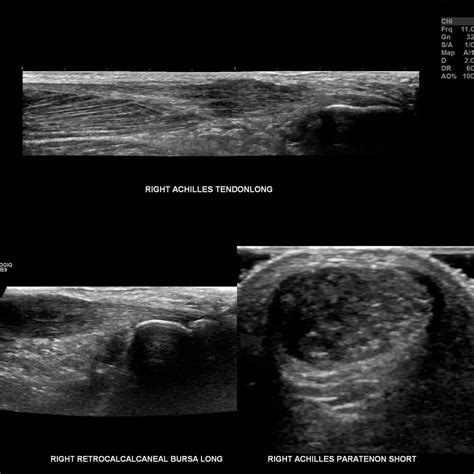

Diagnosing tendinitis typically involves a physical examination and a review of the patient's medical history. The healthcare provider may also order imaging tests, such as X-rays, ultrasound, or MRI, to rule out other potential causes of the symptoms.

Diagnosing tendinosis typically involves a physical examination and a review of the patient's medical history. Imaging tests, such as ultrasound or MRI, may be ordered to assess the condition of the tendon and rule out other potential causes of the symptoms.